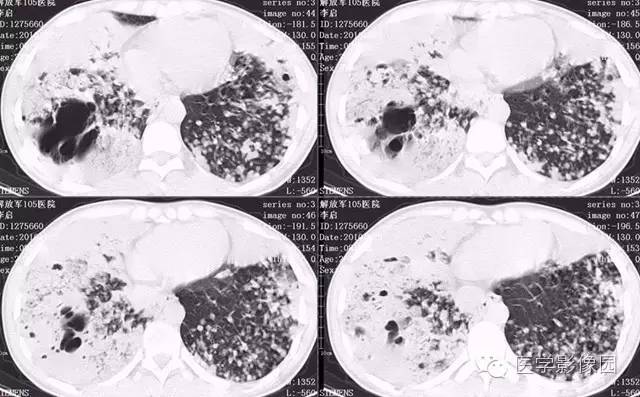

弥漫性肺泡细胞癌1例CT影像表现

病理结果:弥漫性肺泡细胞癌

弥漫性肺泡癌的主要临床及CT表现:临床表现无明显特征, 随着病情的进展, 咳嗽、 咳白痰、 进行性气促。CT表现 为病变分布有两种情况:病变累及一个肺段或肺叶;病变广泛分布于两肺。可归纳为5个特征性征象:蜂房征;支气管充气征;磨玻璃征;血管造影征;两肺弥漫分布的斑片状与结节影。